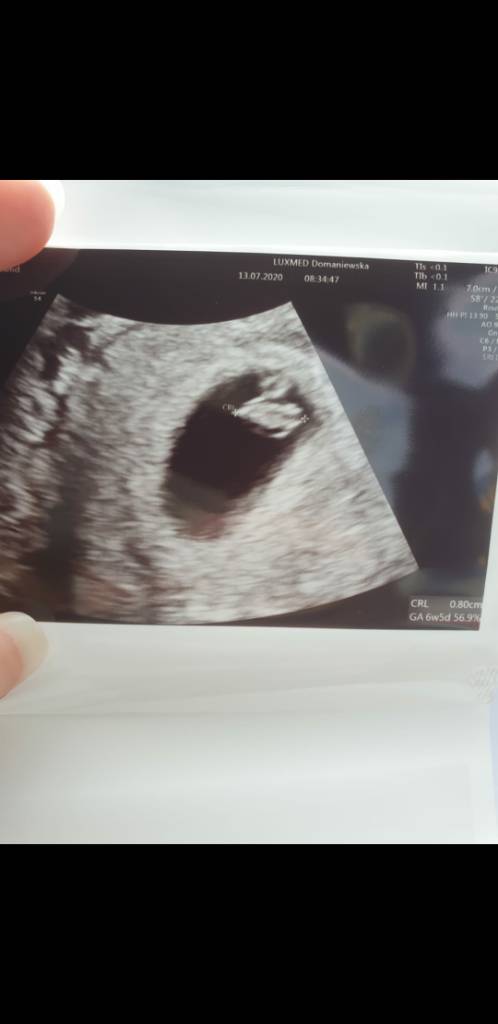

Ja byłam wczoraj na usg, według OM 6t6d według usg 6t5d, serduszko bije więc jedtem trochę spokojniejsza:)

Zobacz załącznik 1148156